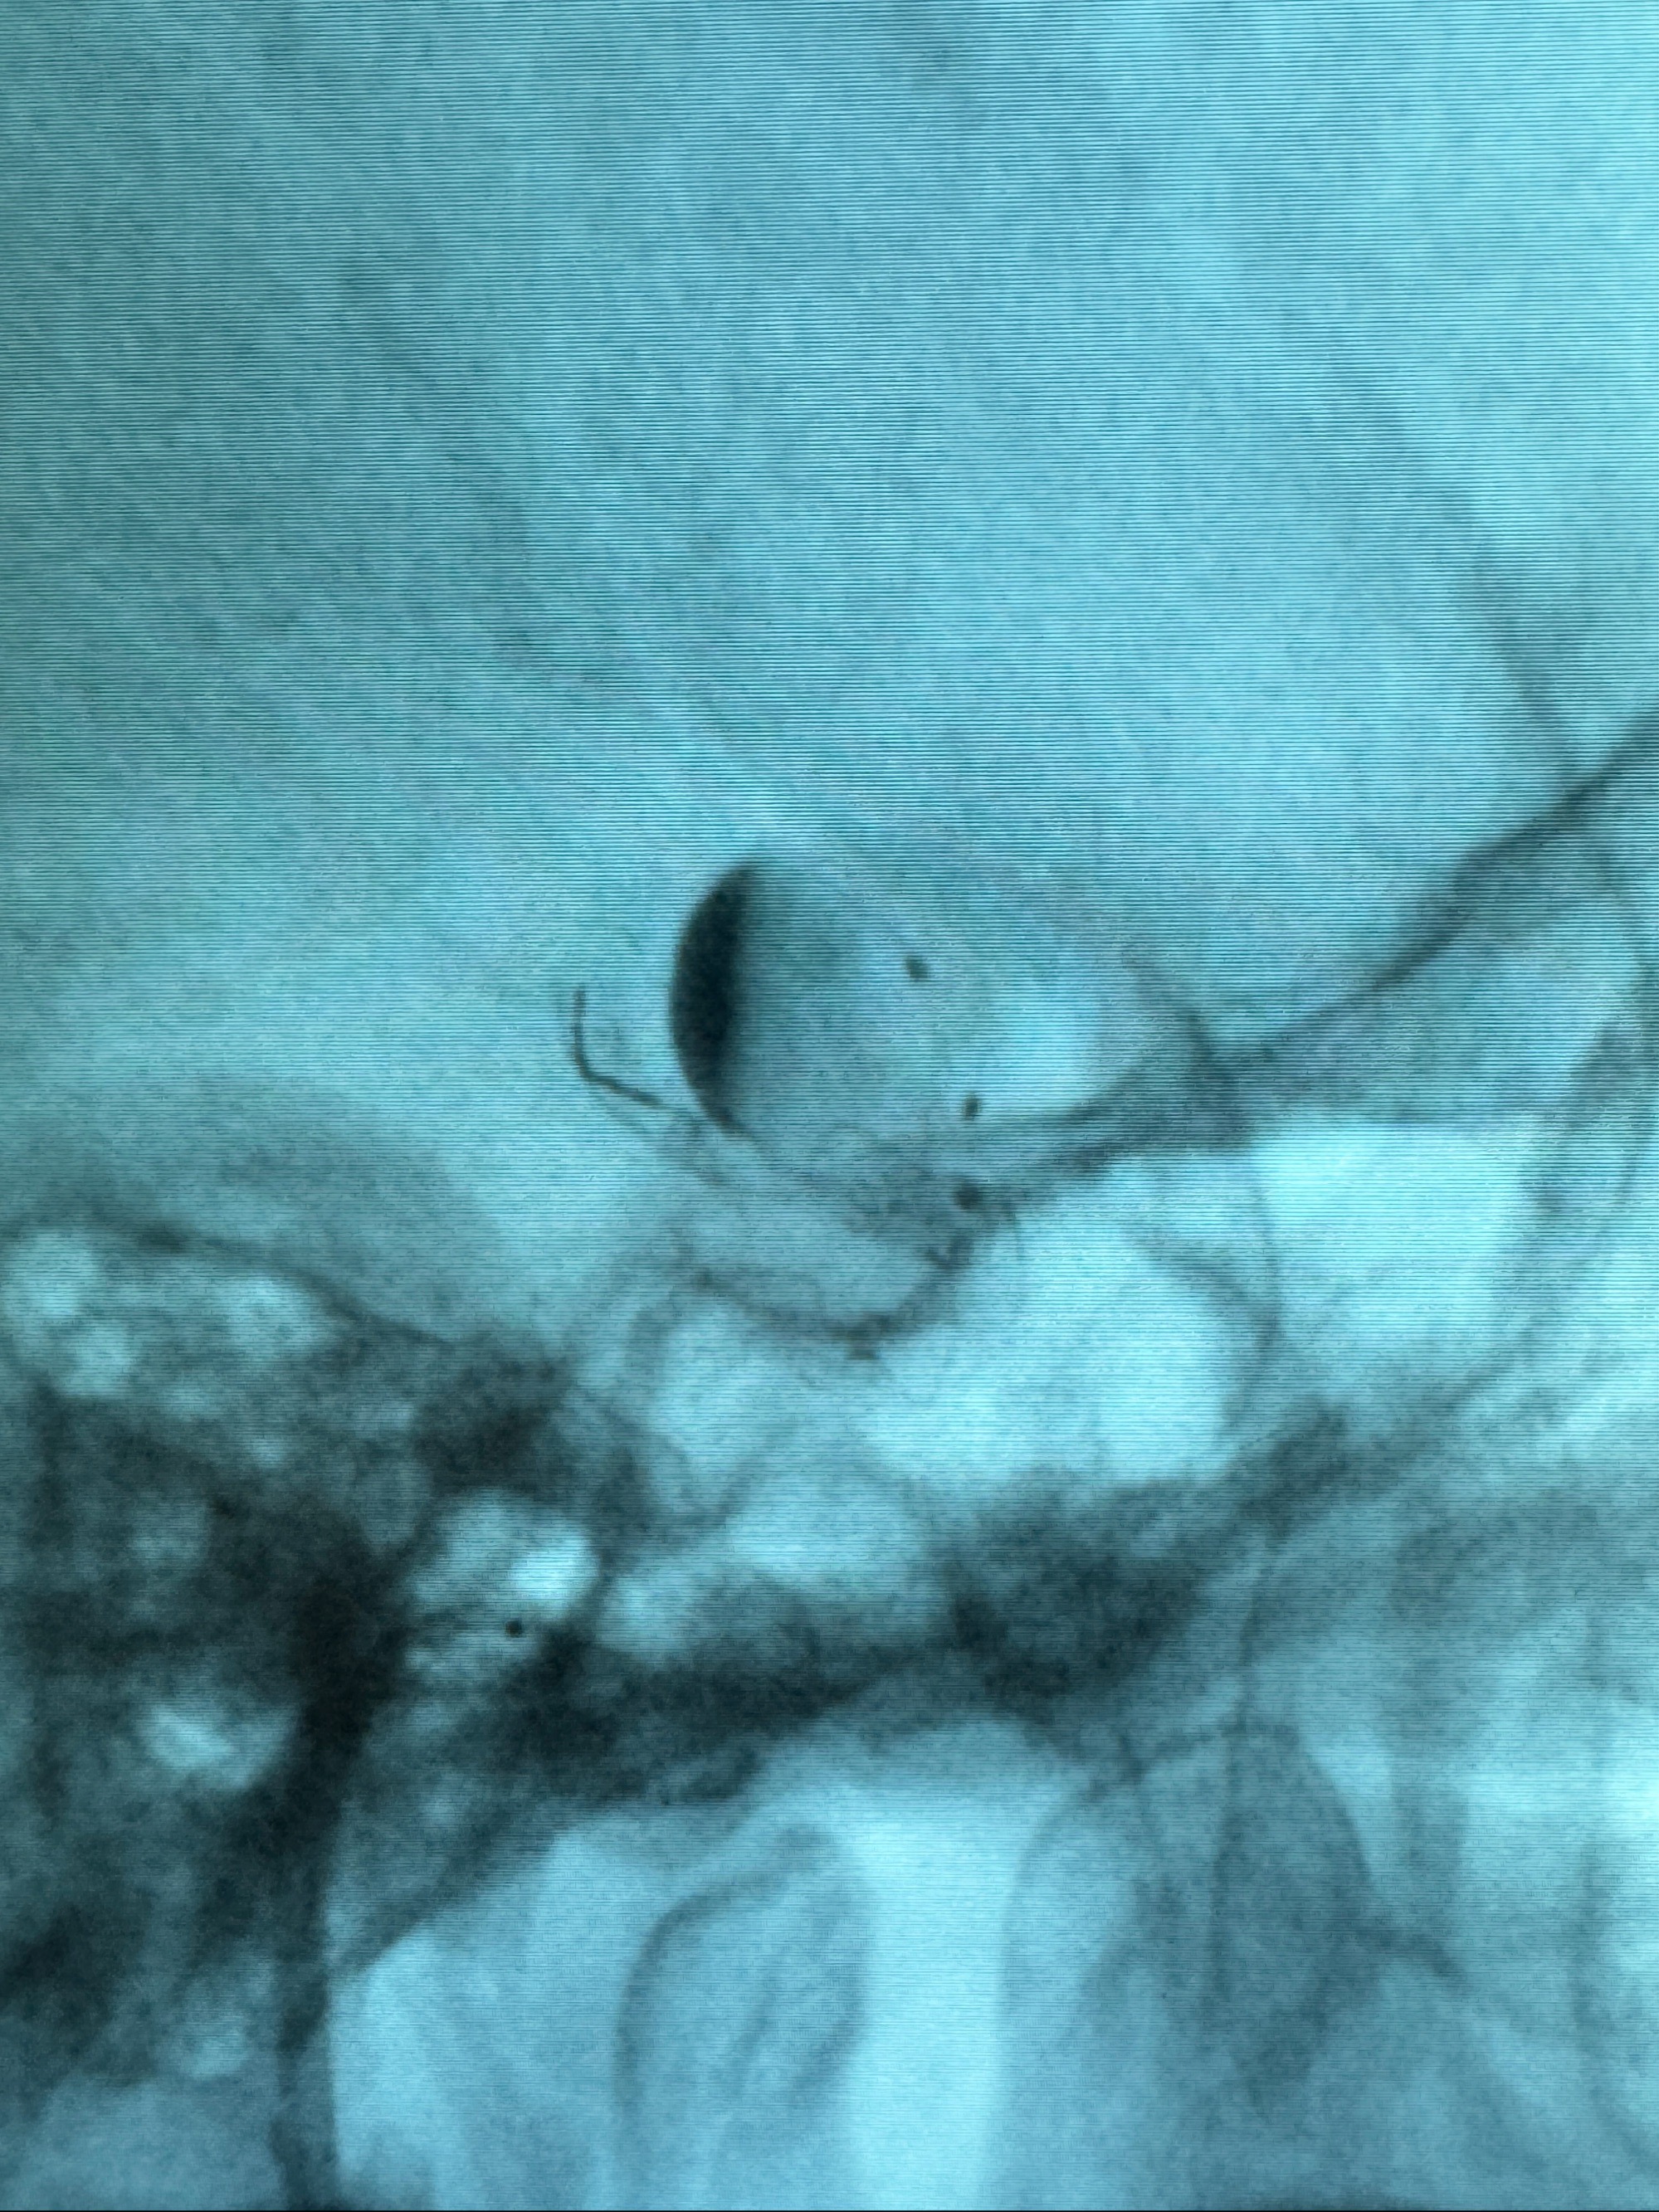

2023-12-08外院DSA:右侧颈眼动脉瘤,约13*12mm大小,压颈试验显示左右向及后向前代偿可

测量动脉瘤的大小:16*13.8*7.6mm大小,较原先变大,考虑双抗后瘤内血栓溶解可能

观察动脉瘤腔内的血流动力学情况